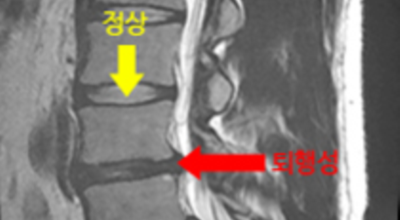

여러 개의 작은 척추뼈가 모여서 척추라는 신체의 기둥을 이루게 돼요. 척추뼈 사이에는 척추뼈끼리 부딪치는 것을 방지하는 쿠션 같은 역할을 하는 '디스크(disc)'라는 말랑말랑한 젤리 같은 구조물이 있는데 우리말로는 '추간판'이라고 합니다.

디스크(추간판)의 한가운데에는 젤리같이 찐득찐득한 '수핵'이라 하는 물질이 들어 있어요. 그 주변에 수핵을 둘러싸는 '섬유륜'이라 하는 두꺼운 막이 있는데 디스크는 전체적으로 자동차의 타이어와 같은 형태라고 합니다.

디스크는 일어선 상태에서는 중력을 받아 납작해져서 바깥쪽으로 약간 볼록한 형태가 된다고 합니다. 디스크는 그 특수한 구조 때문에 웬만한 힘이 가해져도 효율적으로 쿠션 역할을 할 수 있겠습니다. 그러나 급작스럽게 무거운 물건을 들어 올리거나, 부자연스러운 자세를 오랜 시간 취하면 디스크에 무리한 힘이 가해지면서 디스크가 밖으로 돌출이 되게 돼요. 심한 경우 디스크를 감싼 막이 터지면서 그 안에 있는 수핵이 튀어나오게 돼요.